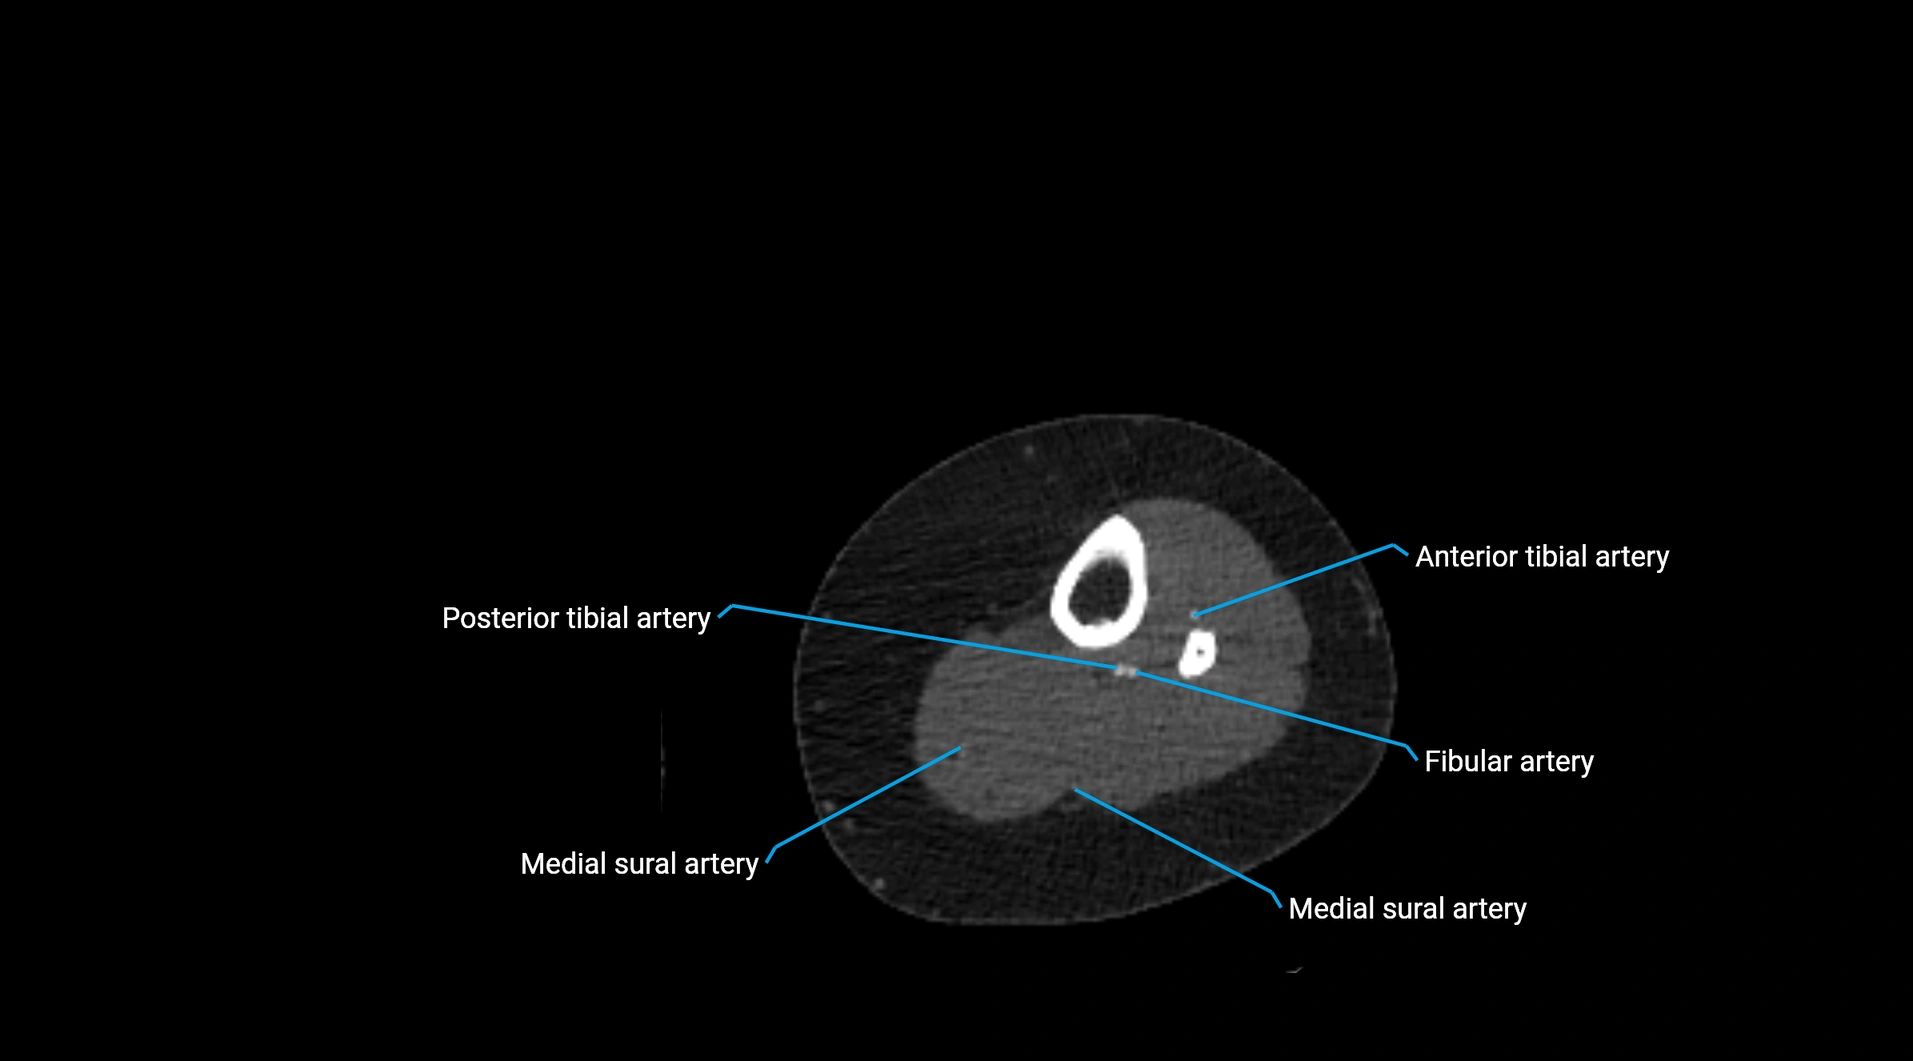

CT images

image